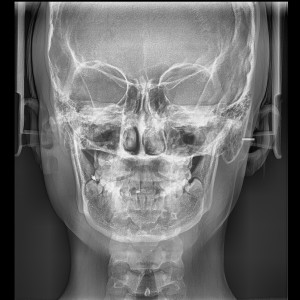

SERVICIOS 2D

SIALOGRAFIA